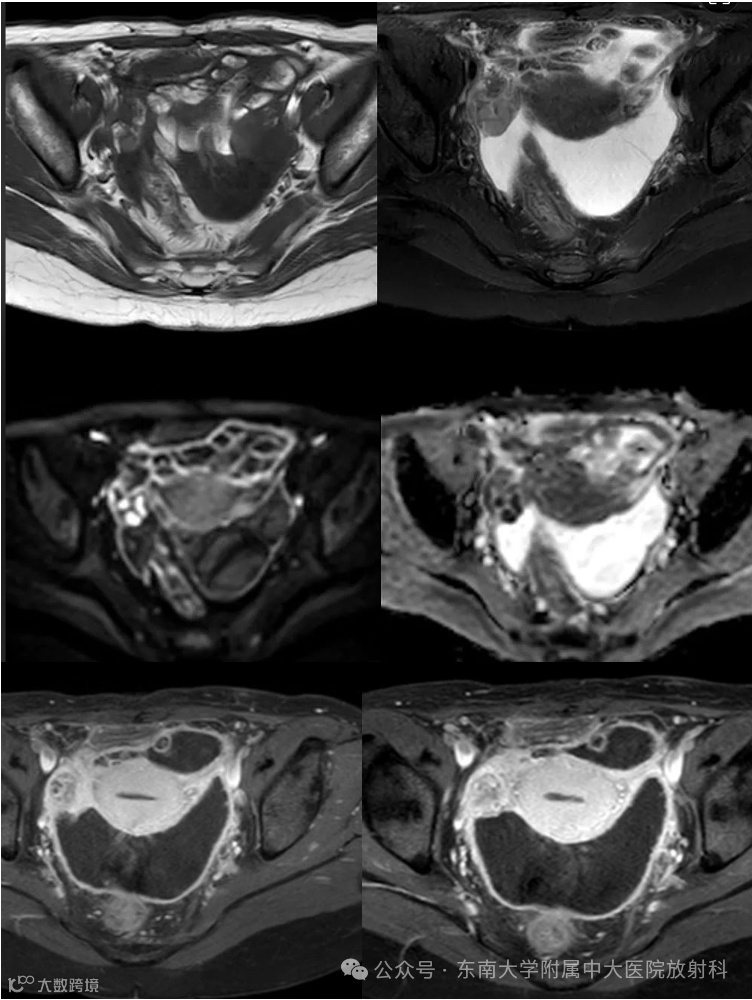

病例2

女,27岁 -

主诉:腹胀1周 -

现病史:1周前自觉腹胀,有恶心,无明显腹痛呕吐,无异常阴道出血,无腹泻便秘等,于外院就诊查CA125:791.8U/ml,左侧卵巢内见一19*18mm液性暗区,腹盆腔见深约65mm液性暗区。遂住院于腹腔穿刺,每日约1000ml左右,淡黄色,腹水脱落细胞可见淋巴细胞。今为求进一步诊治来我院就诊

影像学表现